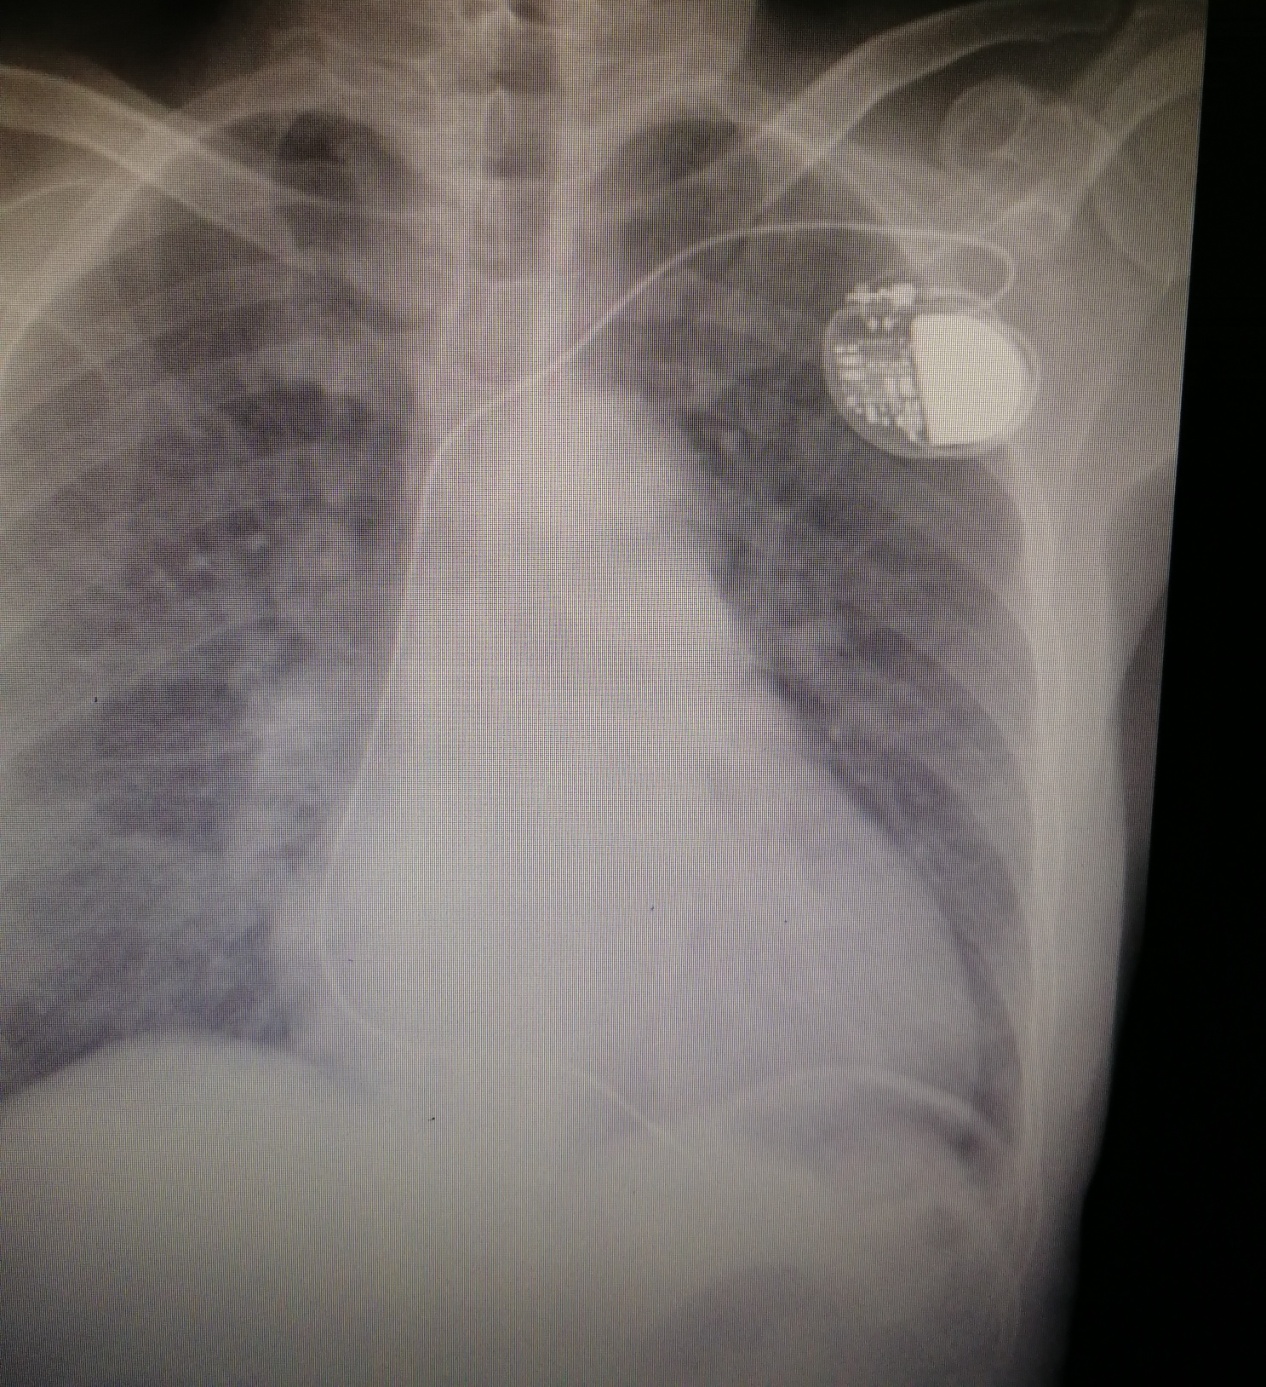

Alberto非常感谢中国医疗队对他的帮助,术后第二天查房时他对医生们说,现在感到特别轻松、头脑特别清醒,再也没有感受到头晕的痛苦了。术后胸部X片及心脏彩超均提示起搏器电极位置良好,没有气胸、心包积液等并发症,心电图也提升起搏功能良好。出院时得知他可以恢复正常生活,不需要再服用治疗心跳慢的药物时,Alberto显得特别高兴,因为他终于能像从前一样跟朋友们一起玩扑克牌了。他反复说着要感谢中国医疗队和中国医生,因为有他们的帮助他才得以重获新生。

术后胸片正面

术后胸片侧面